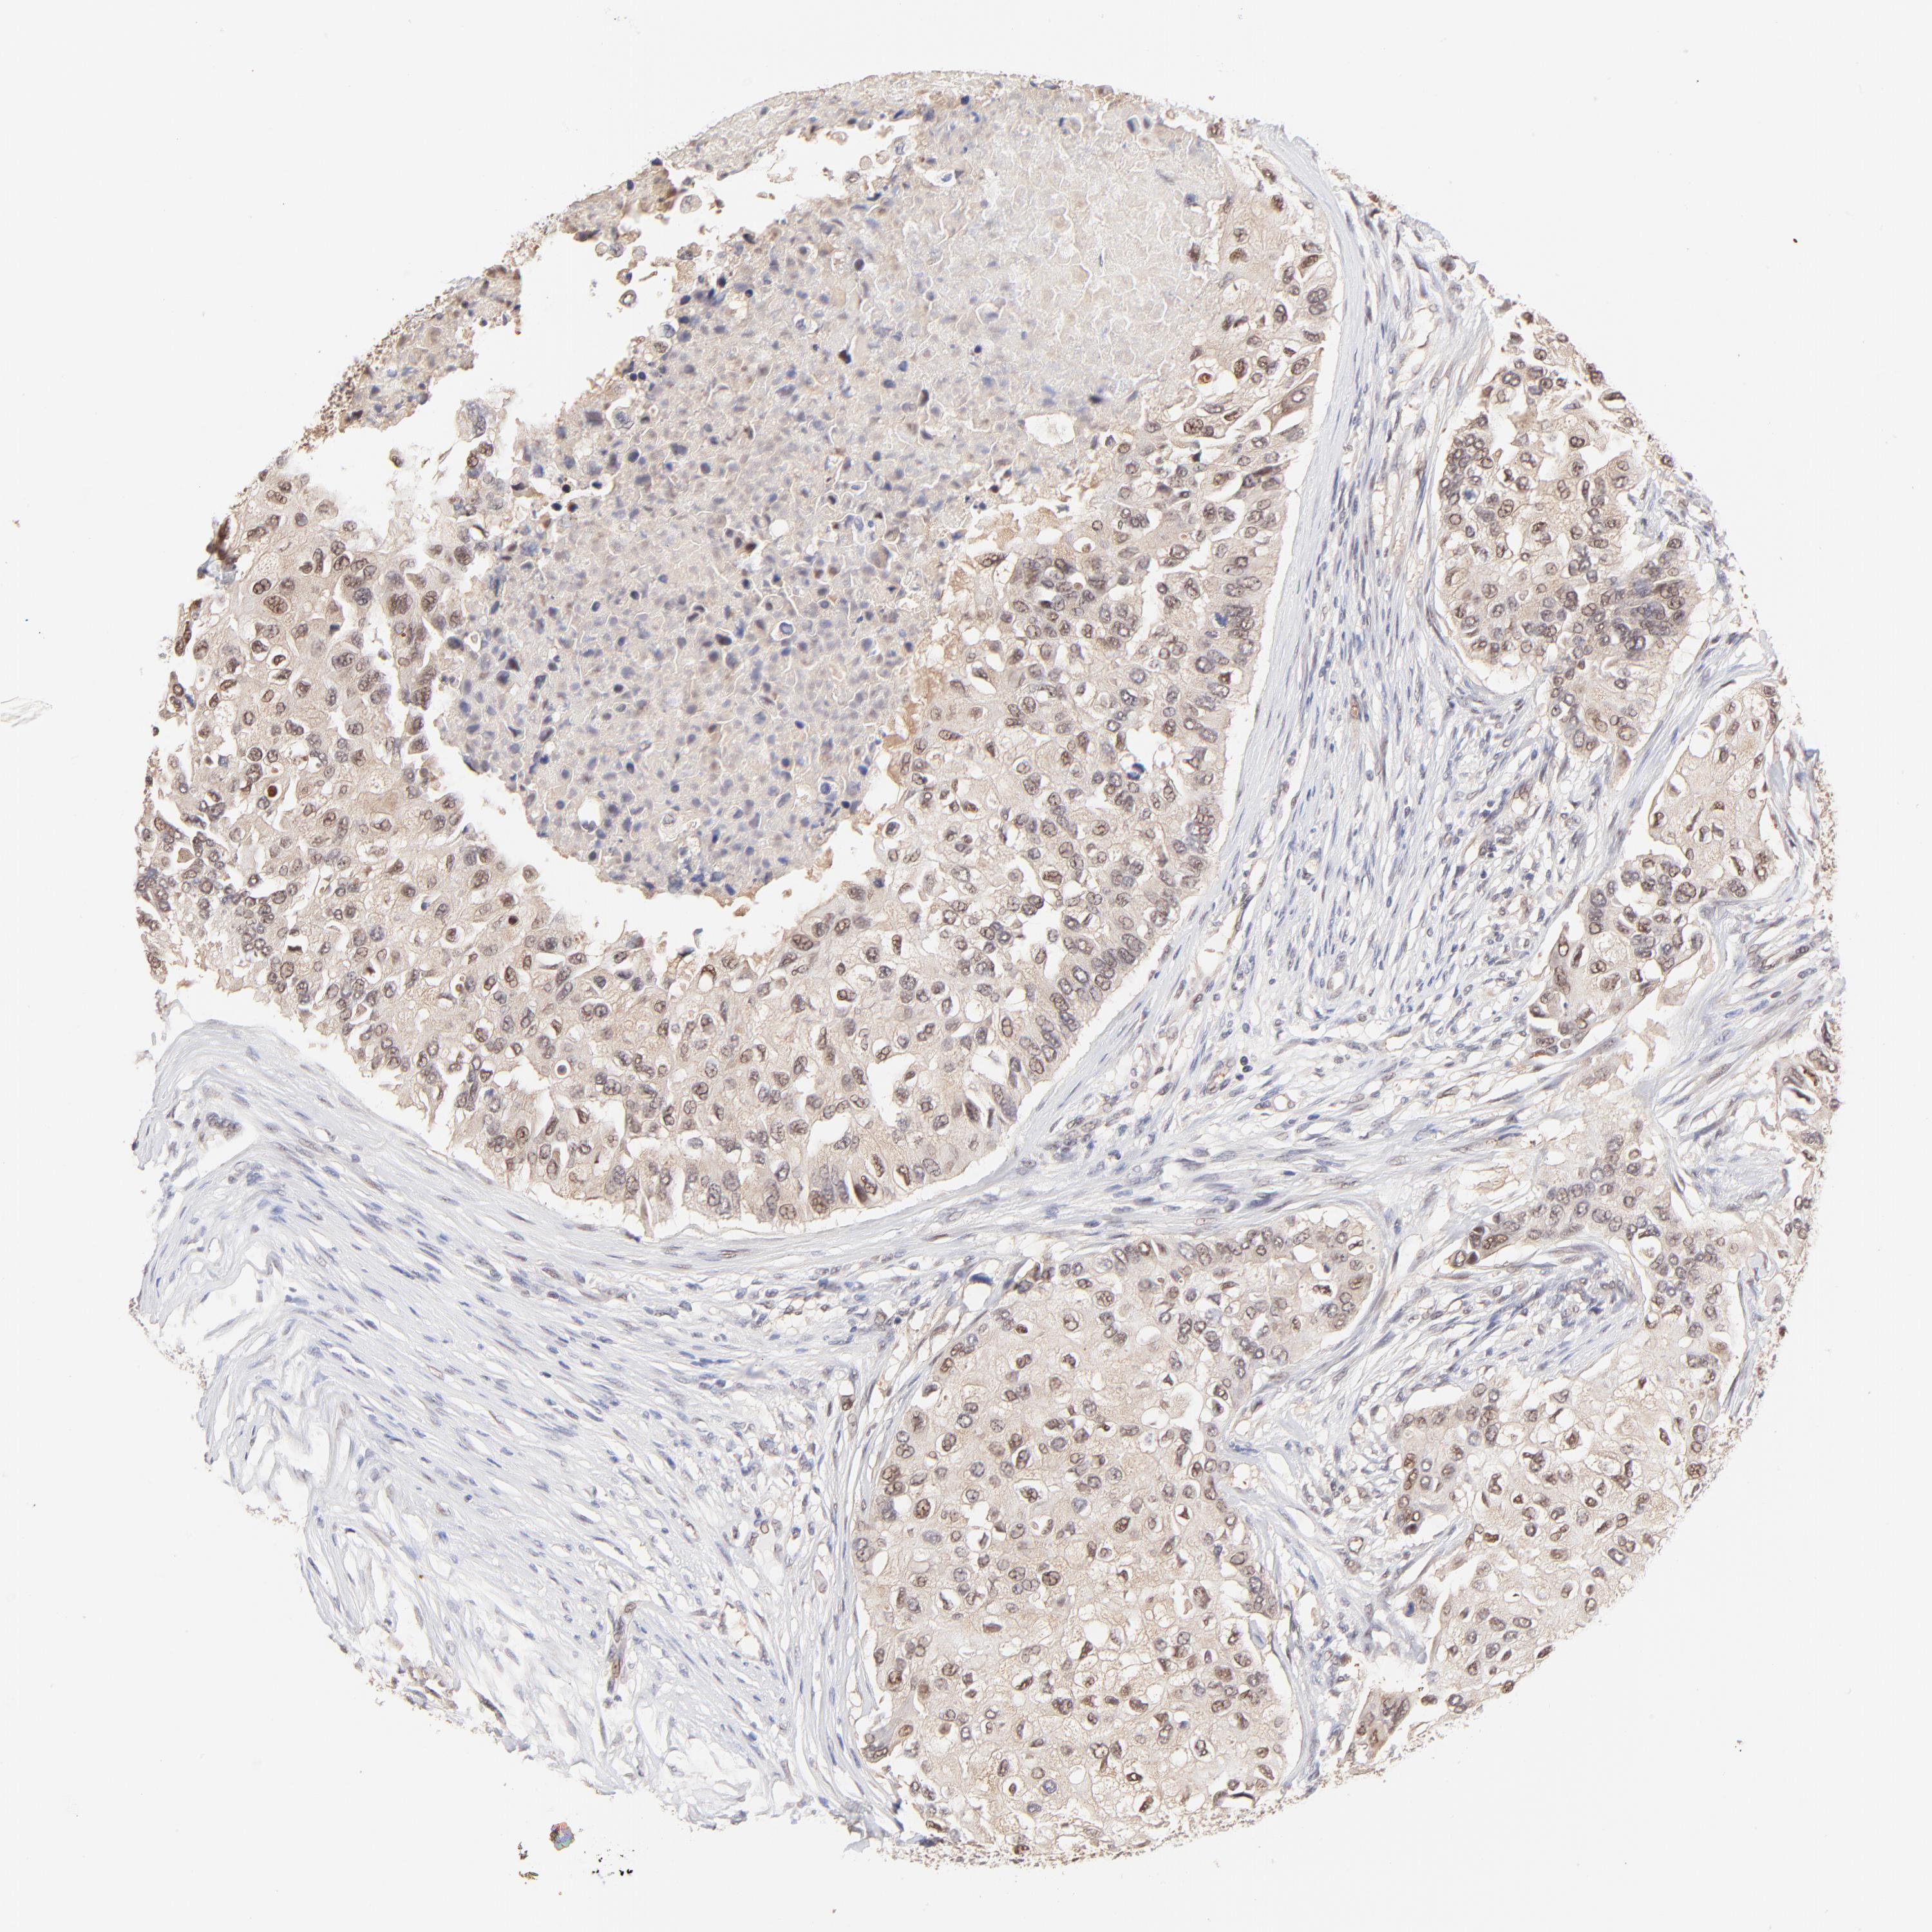

CANCER BREAST CANCER Show tissue menu

Breast cancer

Human cancer